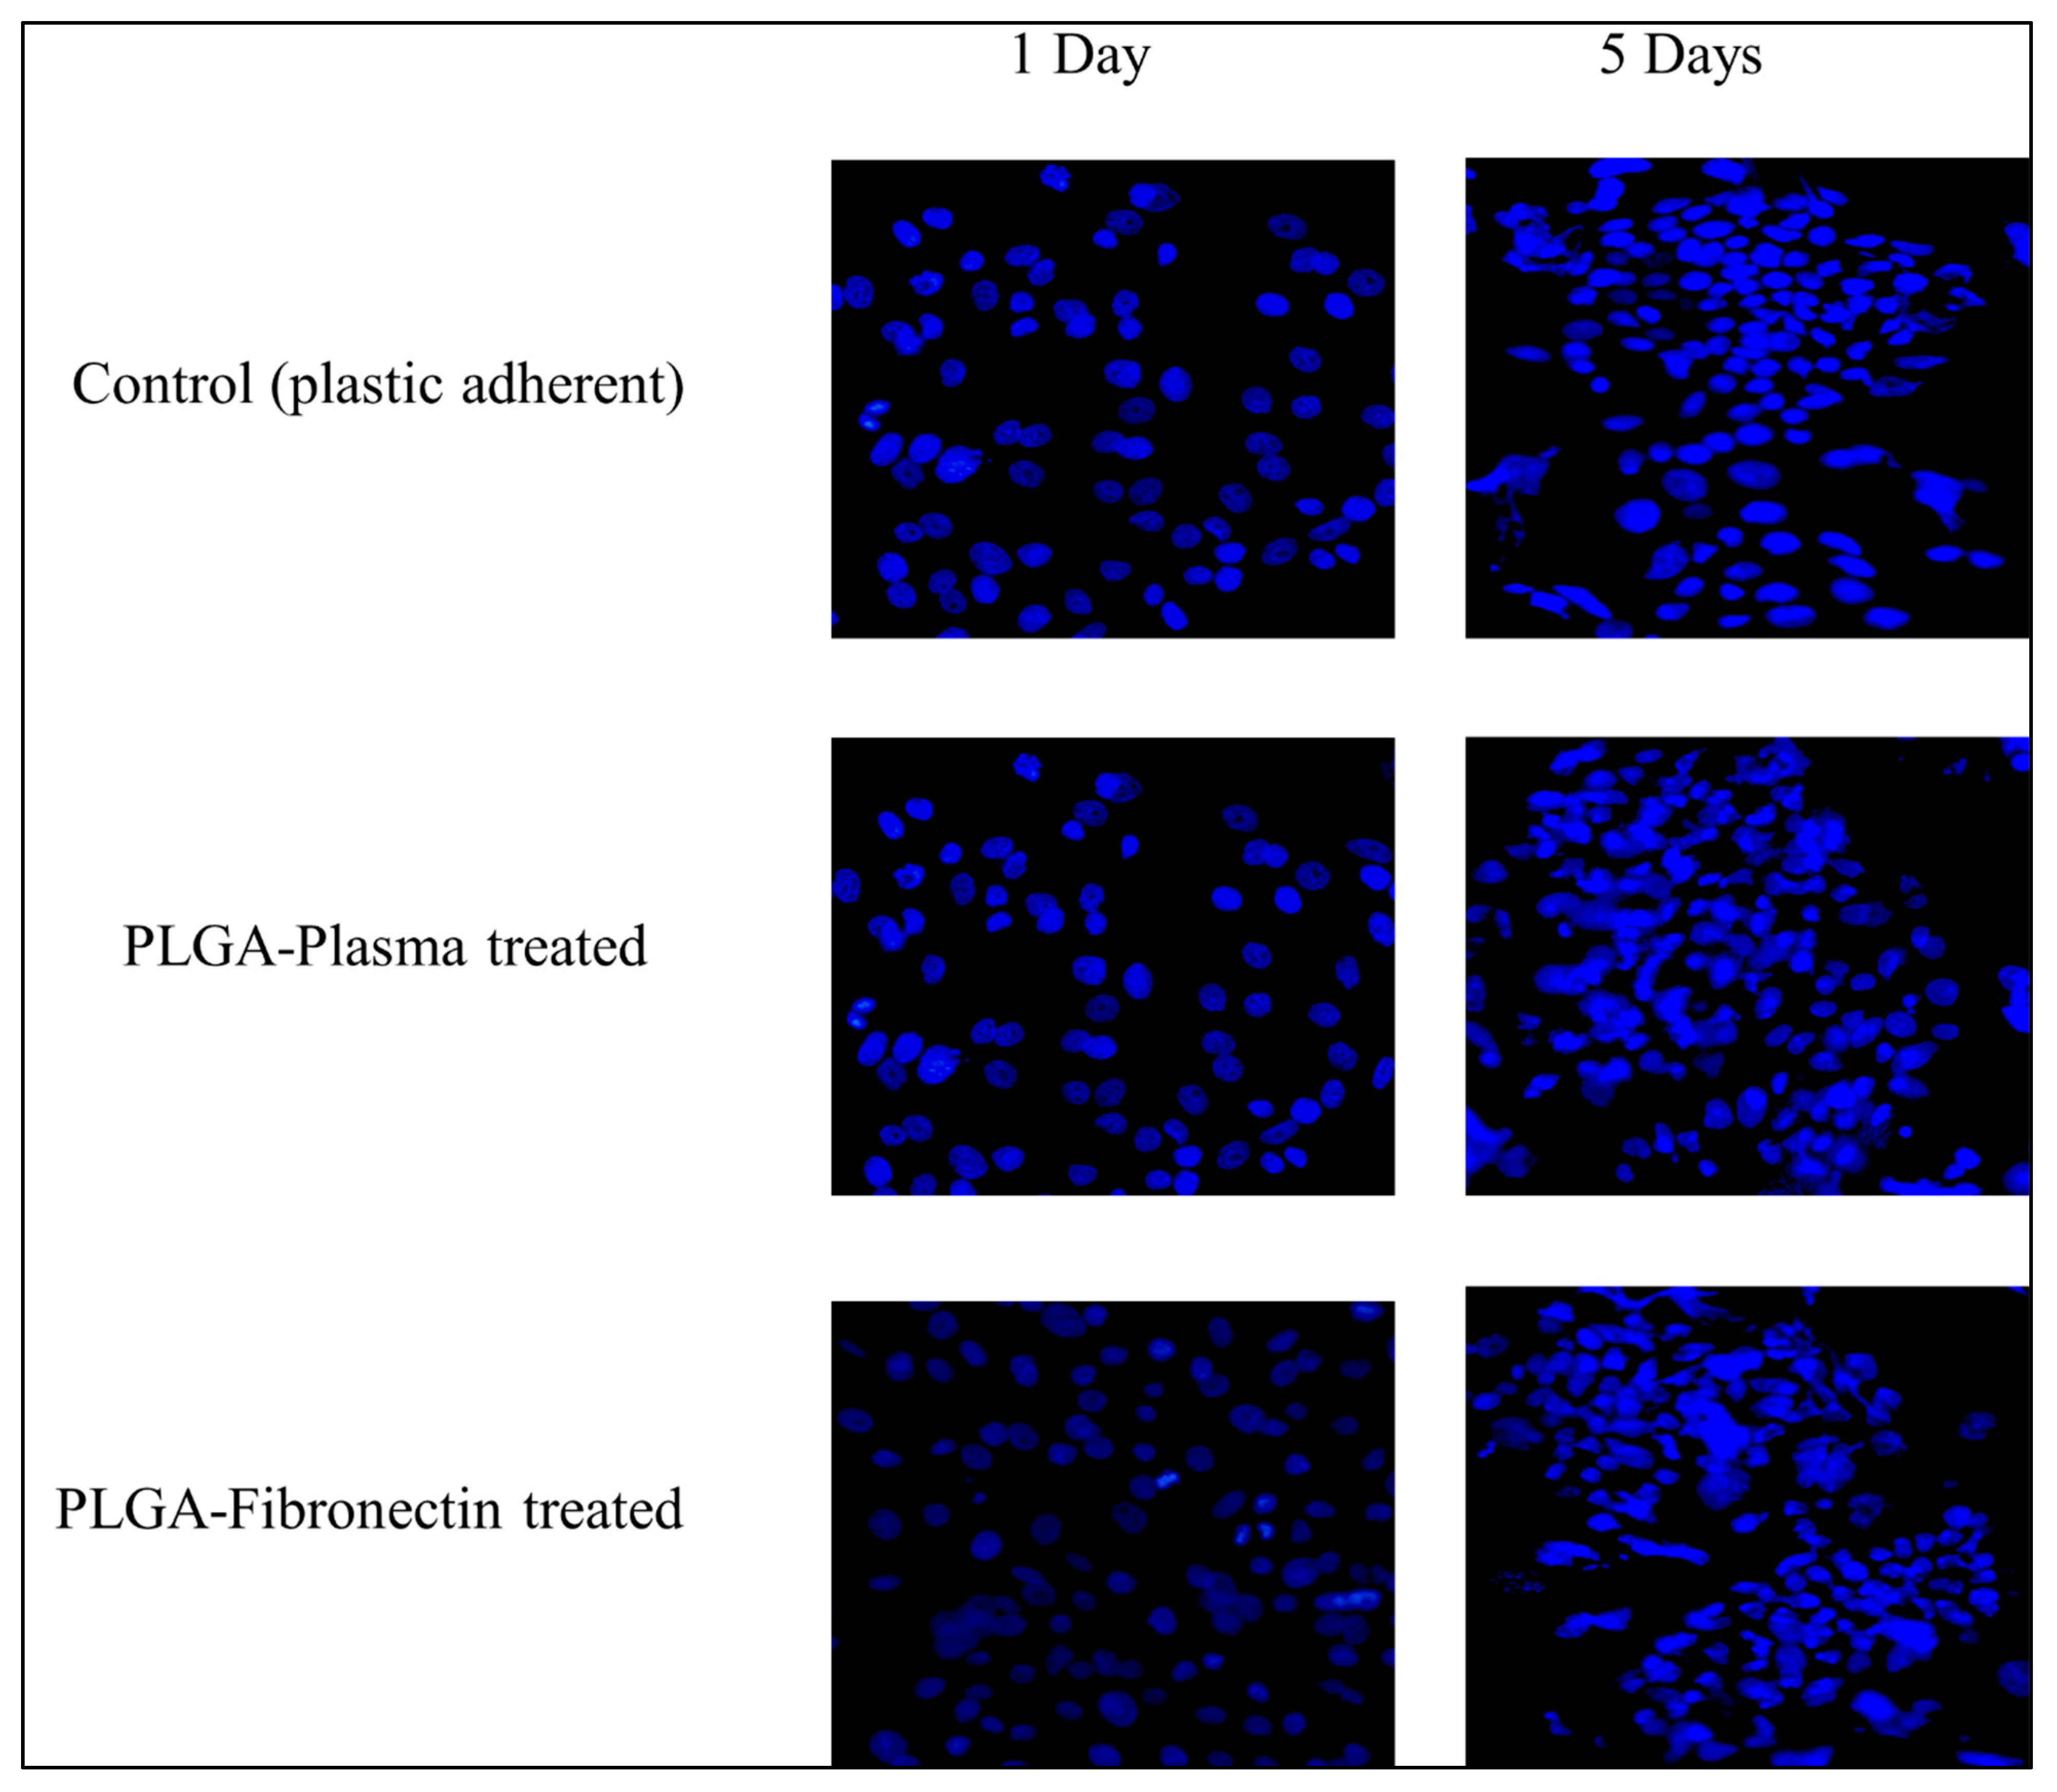

3.4.1. Cell Attachment

3.4.2. Cytotoxic Assay